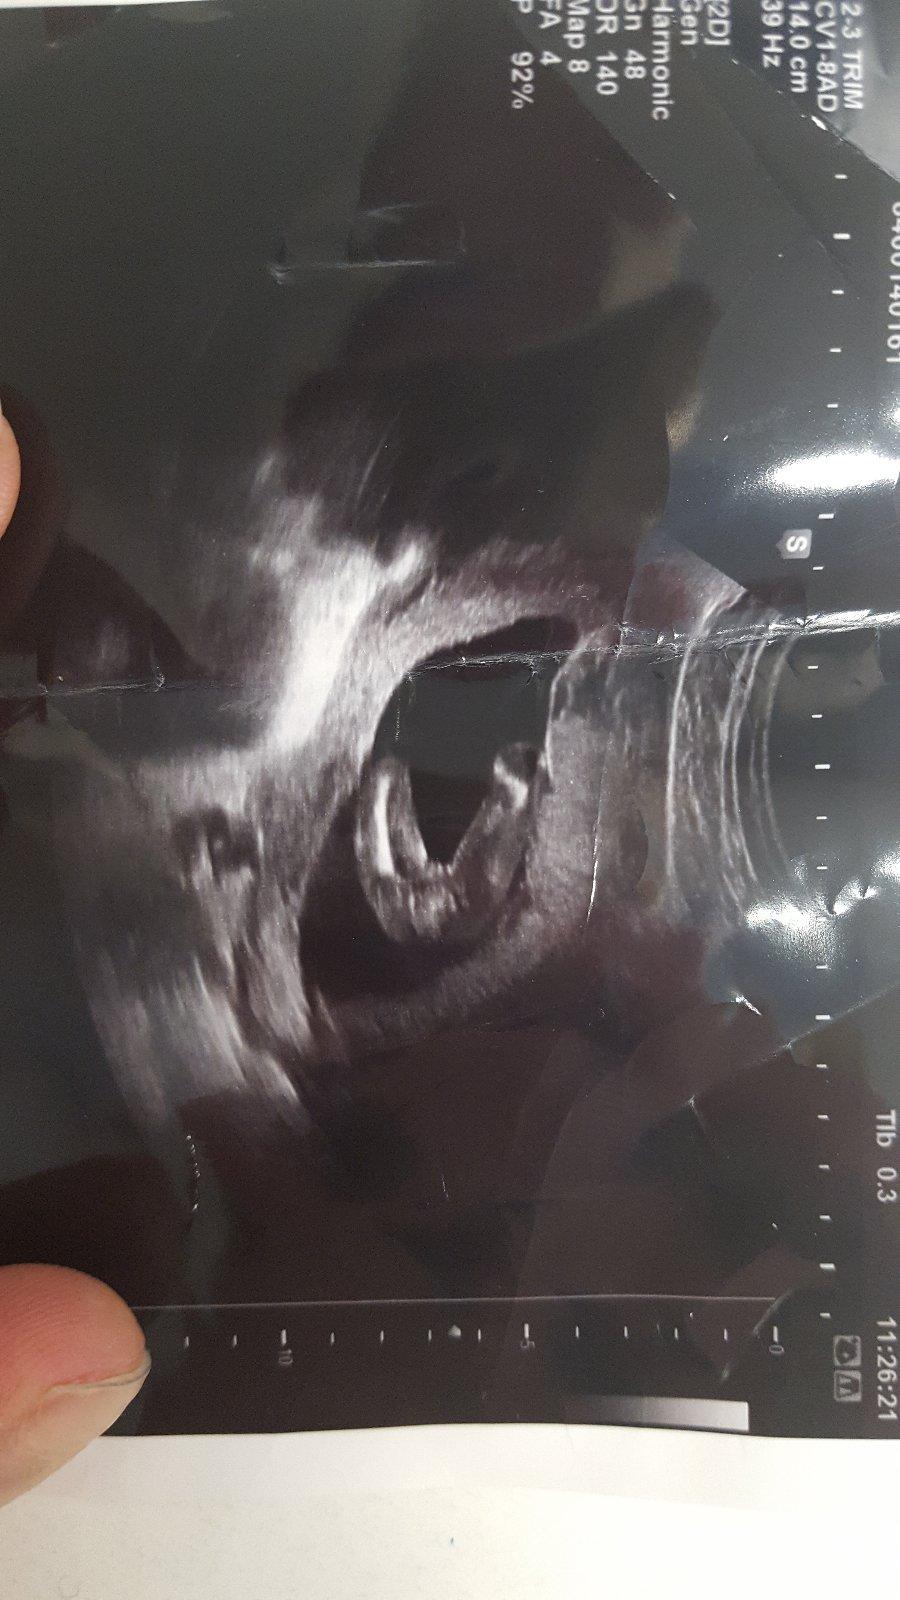

Ahoj maminky a budoucí maminky 😉 Prosím, poradila byste mi některá, co vidíte na fotce z ultrazvuku ve 20. týdnu za pohlaví? Určitě jste foteček viděly už mraky, proto vás žádám o radu...Nechci nikoho ovlivnit, proto svůj tip řeknu později 🙂 Děkuju moc!!!

@andy11111 tipla bych to na holčičku, mám doma podobný obrázek a už vím určitě, že to bude holčička 🙂

@tomikjoejoe Vypada to tak,ale porad si davam nejakou nadeji,ze by ten pinda mohl byt jeste schovany🙂 Ale,kdyz to bude holka,tak ji budu mit stejne rada jako kluka;)

@mariejosef To urcite,jsem za ni rada.Jen jestli se treba nekomu nestalo,ze se z tohodle objevil jeste pinda🙂